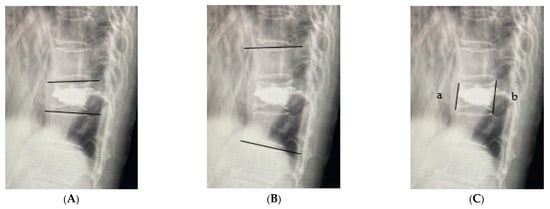

| Preoperative vertebral wedge ratio (%) | 69.5 ± 2.49 | 76.2 ± 1.13 | p < 0.05 |

| Immediately postoperative vertebral wedge ratio (%) | 86.5 ± 1.58 | 88.6 ± 0.72 | N.S. |

| Final postoperative vertebral wedge ratio (%) | 78.7 ± 2.33 | 82.1 ± 1.05 | N.S. |

| Preoperative vertebral kyphosis angle | −10.7 ± 0.91 | −9.5 ± 0.41 | N.S. |

| Immediately postoperative vertebral kyphosis angle | −4.7 ± 0.59 | −4.4 ± 0.27 | N.S. |

| Final postoperative vertebral kyphosis angle | −7.9 ± 0.86 | −6.6 ± 0.39 | N.S. |

| Preoperative local kyphosis angle | −11.3 ± 2.54 | −6.3 ± 1.16 | N.S. |

| Immediately postoperative local kyphosis angle | −0.9 ± 3.05 | −1.1 ± 1.39 | N.S. |

| Final postoperative local kyphosis angle | −11.2 ± 2.74 | −5.2 ± 1.23 | p < 0.05 |